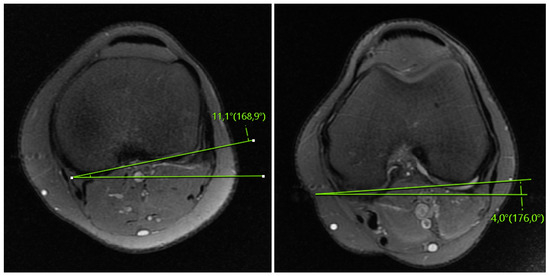

Does Rotation and Anterior Translation Persist as Residual Instability in the Knee after Anterior Cruciate Ligament Reconstruction? (Evaluation of Coronal Lateral Collateral Ligament Sign, Tibial Rotation, and Translation Measurements in Postoperative MRI)

2.1. MRI Evaluation Methods